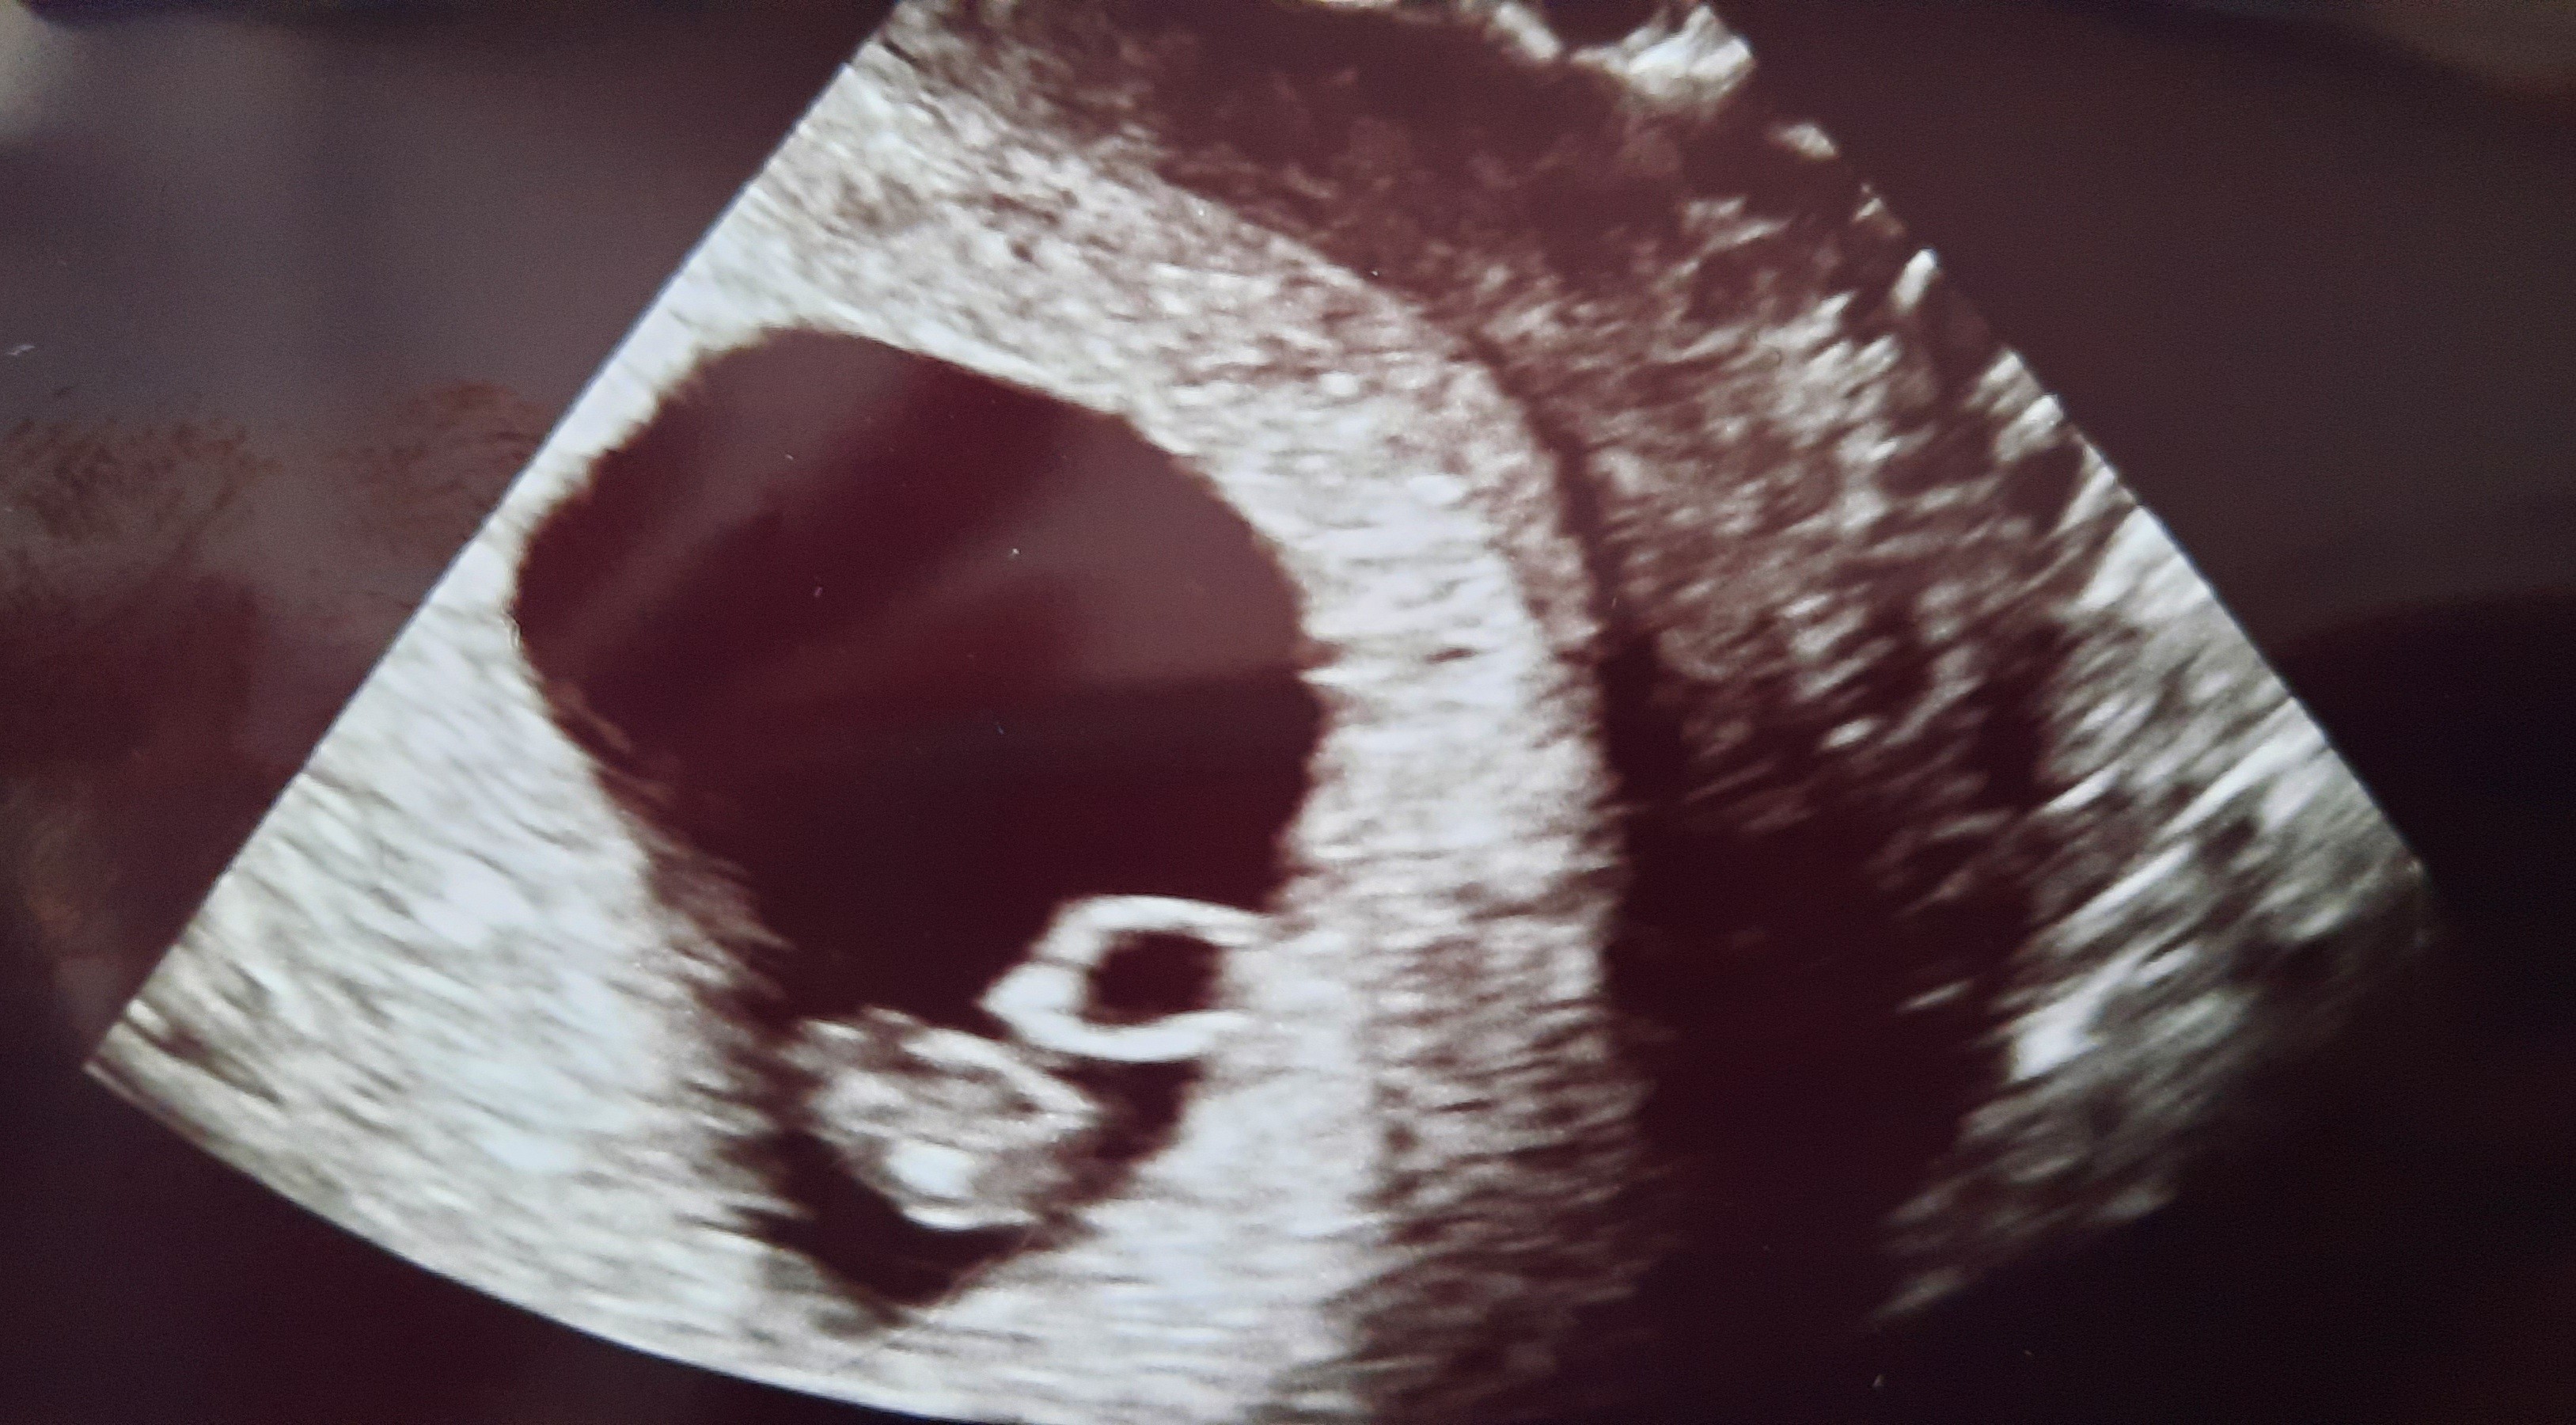

Ja już po wizycie, jestem w 6t5d, jest zarodek crl 8,1 mm. Widziałam jak serduszko bije 😍ale lekarz nie mierzył tętna. Kolejna wizyta 03.11, a wcześniej mam wykonać badania krwi :)

Załączniki

• 20211011_141116.jpg

20211011_141116.jpg

1,1 MB · Wyświetleń: 109